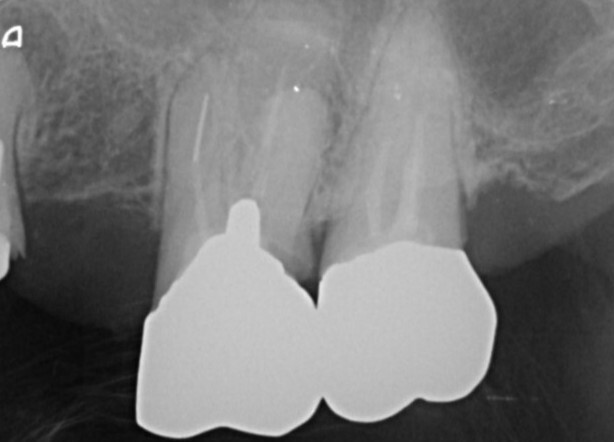

根管の状態によってはMTAセメントの使用

強い殺菌作用と高い封鎖性を持つMTAセメントを、症例に応じて使用します。難治性の根管や根の先に病変がある場合でも、治癒を促す効果が期待できます。

破折ファイル(根管内異物の除去)

過去の治療で根管内に器具が折れて残っている場合でも、マイクロスコープを用いて可能な限り安全に除去を行います。歯を残すための選択肢を広げます。